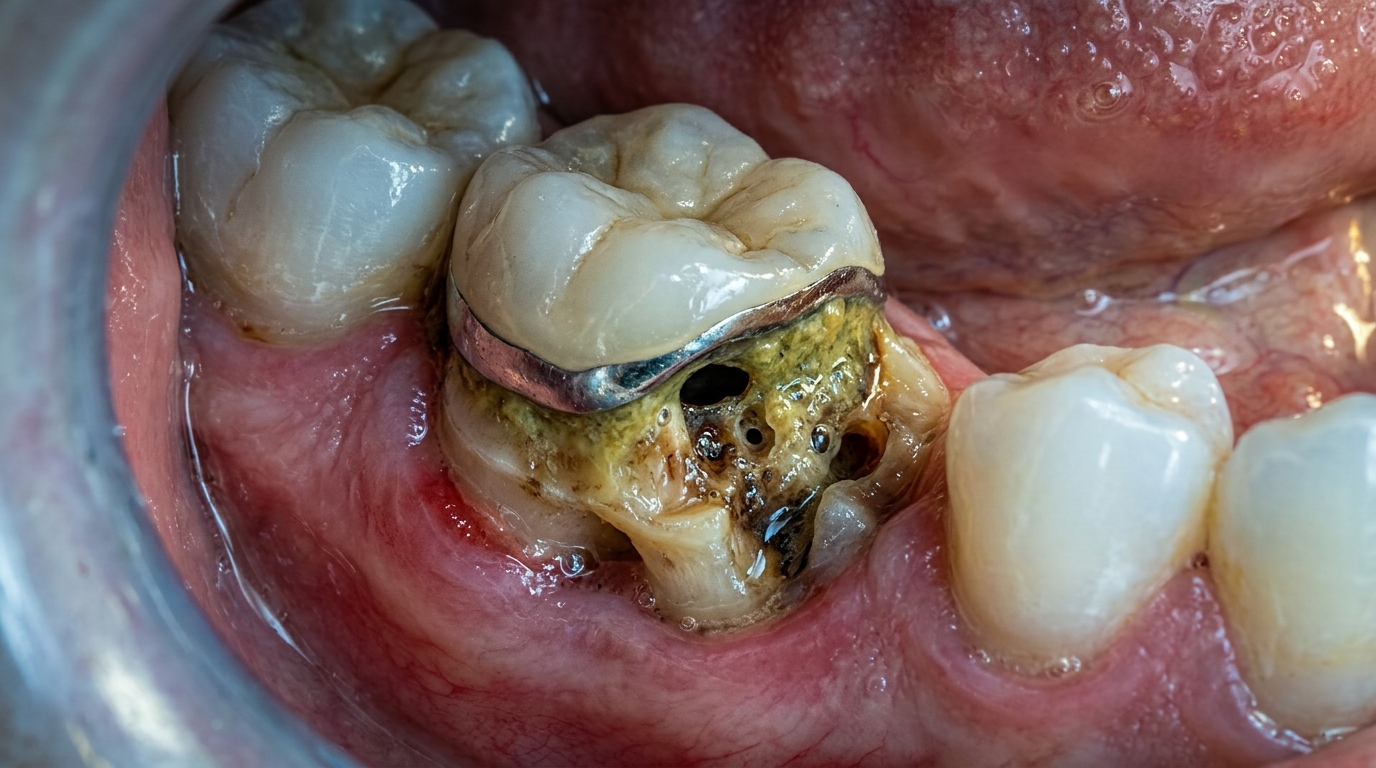

Иллюстрация основных причин запаха из-под коронки: от микрозазоров до инфекции зуба.

Фото симптомов: отек десны, гнойное выделение и расшатанная коронка на зубе.